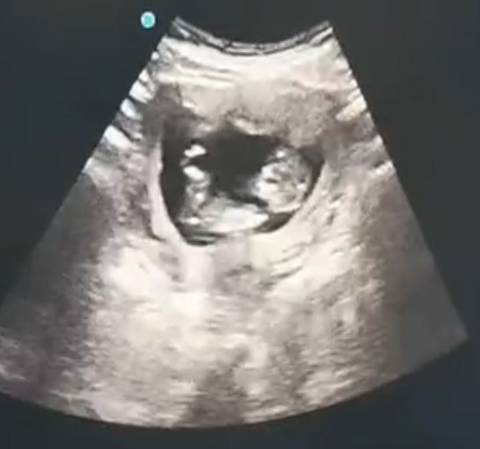

11周大长腿

即将三个月的虎子